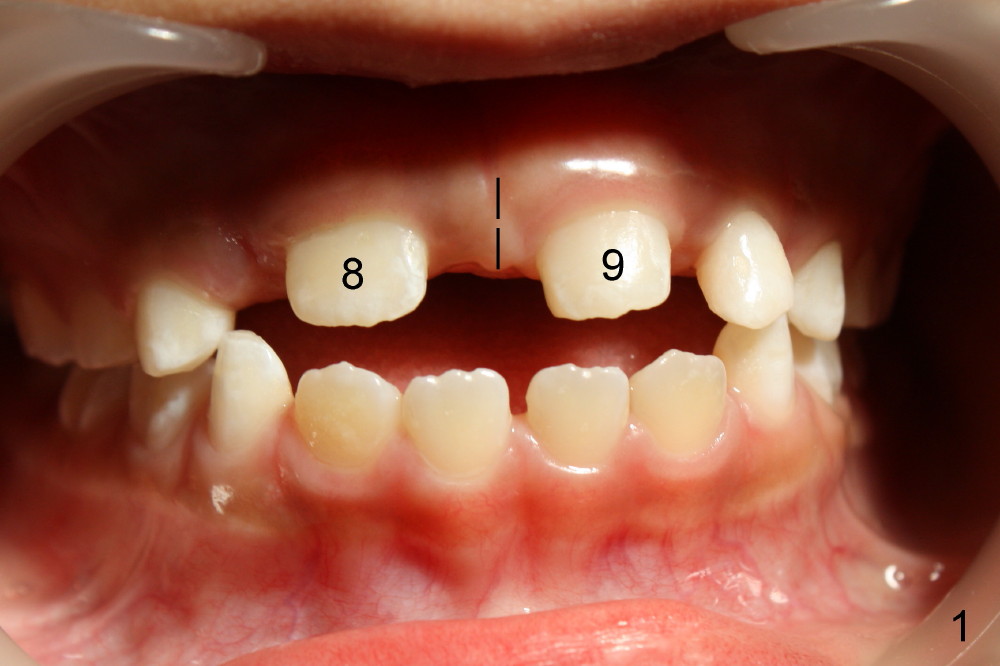

A seven-year-old co-operative boy presented to my office for composite. Exam shows open bite and a large diastema between the erupting upper central incisors (Fig.1-4). His mother notices that the diastema is more due to lateral displacement of the right central than the left central's (compare to Fig.1: black dashed line). She asks whether the uneven displacement will interfere with eruption of the upper right lateral incisor (Fig.2,3, as compared to Fig.4). She is interested in early ortho.

There are three questions. Will the right lateral erupt by itself and the diastema self corrects? When can we start ortho? How can we treat deep cingulum of #9 (Fig.2 >), removing marginal ridges or placing composite in the cingulum? The purpose of cingulum treatment is to prevent caries. Do we also need to add composite to #9 proximal surfaces to make it look as wide as #8? Thanks.